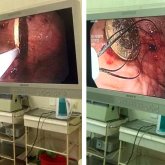

Таразда 9 жасар бала байқамай тиын жұтып қойған (ФОТО)

Дәрігерлер мұндай оқиға жиі болмаса да, ұшырасып тұратынын айтады.